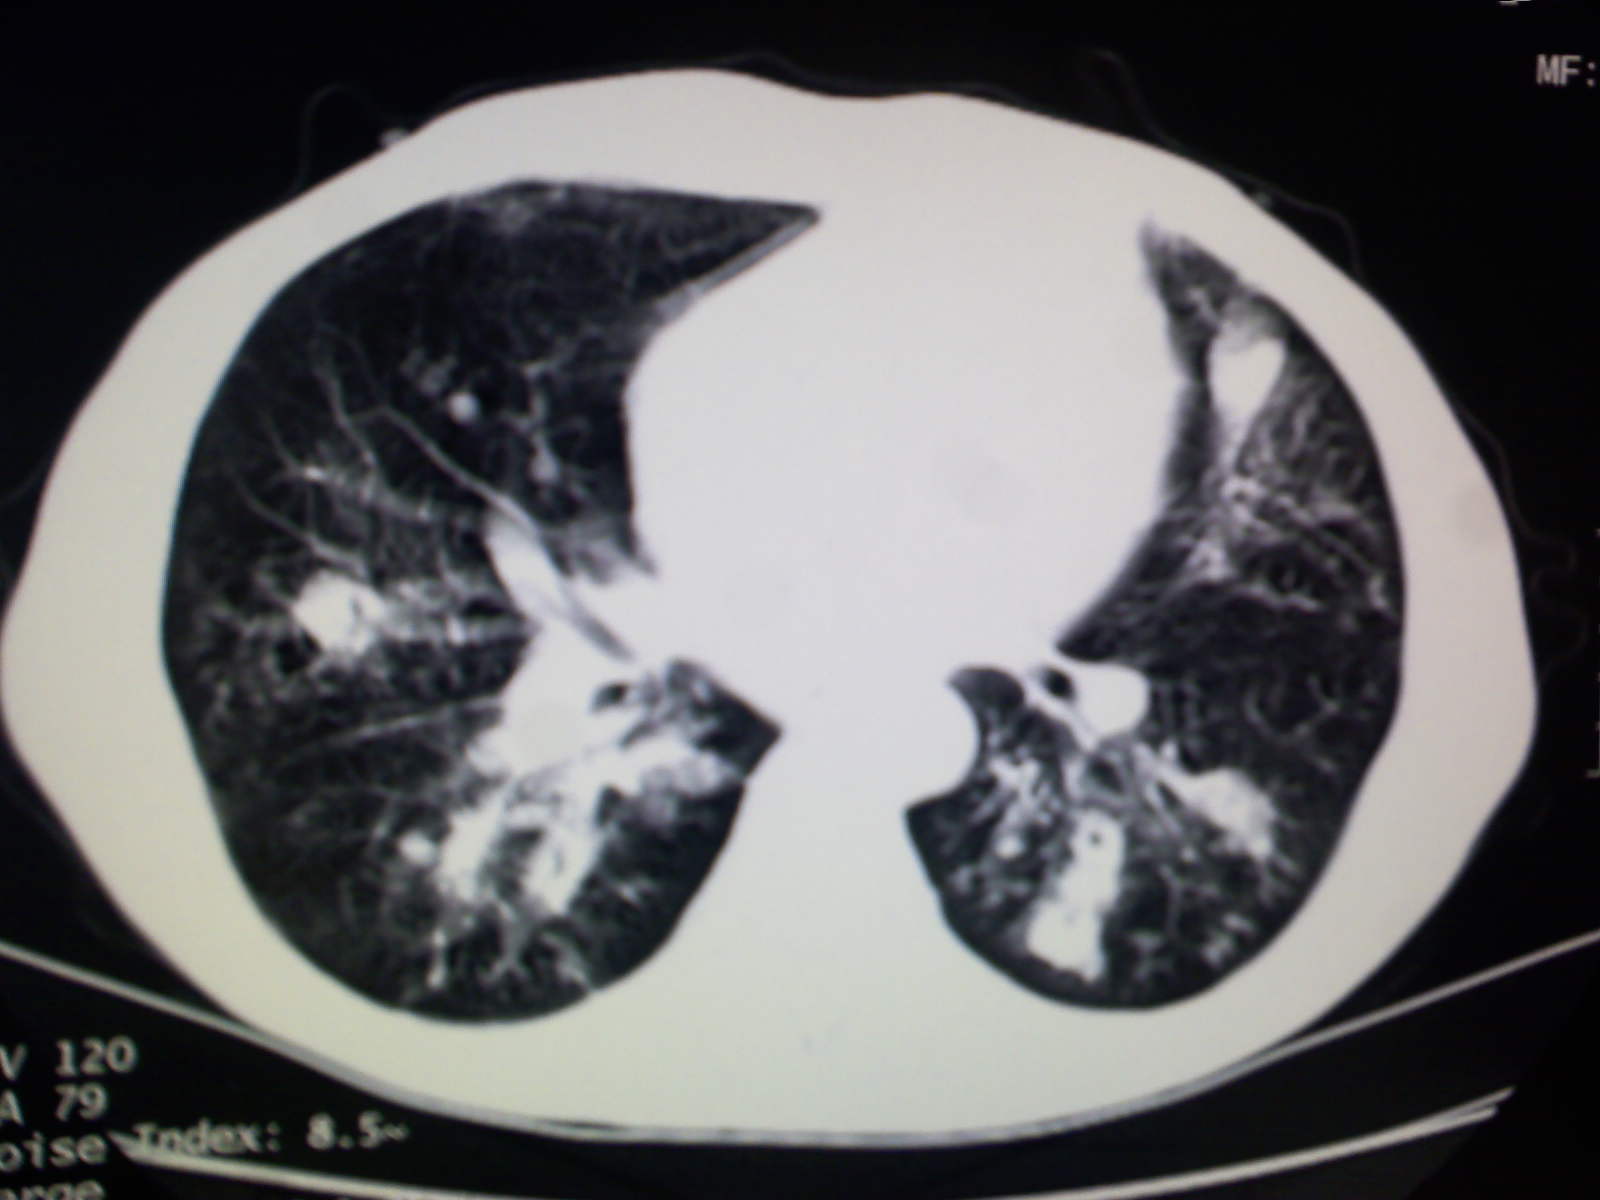

以下是引用卜一在2009-4-11 15:50:00的发言:[br]双肺继发性肺结核伴空洞形成,不排除合并霉菌感染!(病灶呈多形态 多特征 散在分布)。另:合并支气管扩张征伴感染!

以下是引用主力军在2009-4-11 15:55:00的发言:[br]两肺继发性肺结核可能性大。

以下是引用康鹏在2009-4-11 16:30:00的发言:[br]双肺继发性肺结核伴空洞形成合并感染[br]支气管扩张合并感染